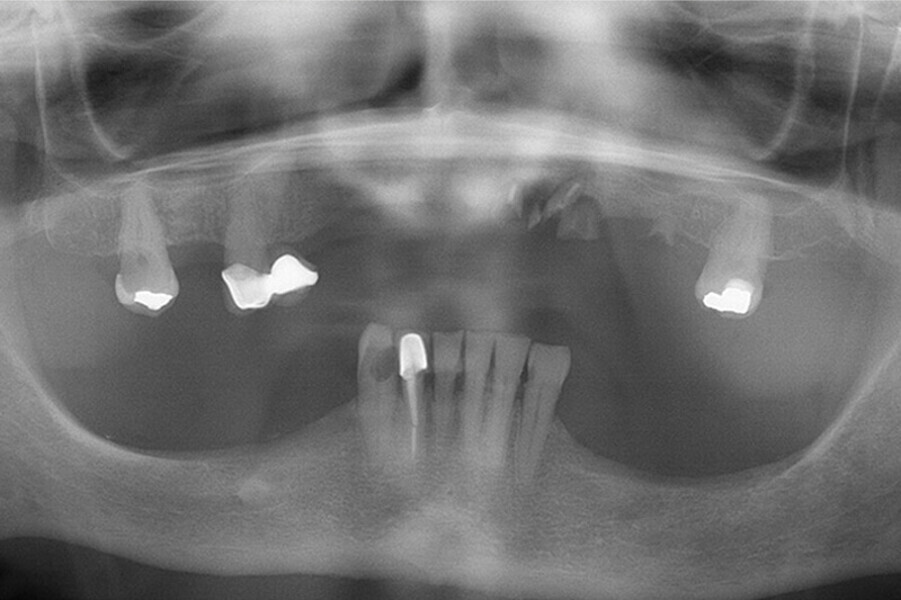

Fig. 24. Rx Pre-operatoria, Prótesis híbrida inmediata con 8 años de evolución y Rx Control a los 8 años.

Fig. 25. Rx Pre-operatoria, Prótesis híbrida inmediata con 8 años de evolución y Rx Control a los 8 años.

Fig. 26. Rx Pre-operatoria, Prótesis híbrida inmediata con 8 años de evolución y Rx Control a los 8 años.